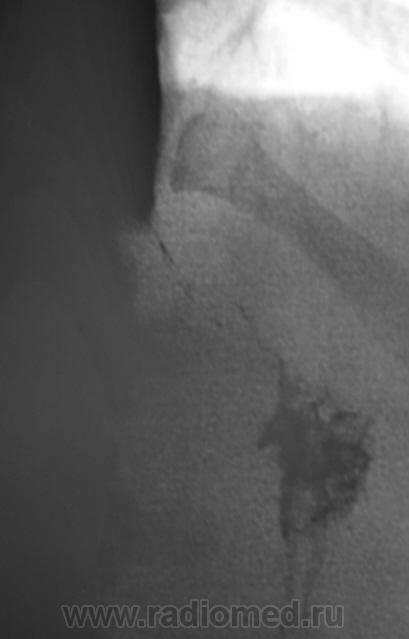

И еще "картинка" через 15 минут.

классика ахалазии кардии, 3 ст. симптом  "мышинного хвоста".

Ахалазия кардии.

+